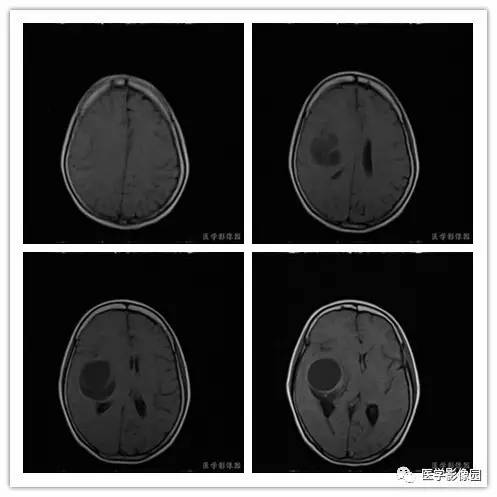

影像学表现:右侧颞叶深部区见一长T1、长T2囊样信号,成明显环形强化、未见明确结节影,没有FLAIR和DWI图,内见分隔,边界较清,周围水肿不明显,右侧脑室明显受压、颞角扩大,右侧脑沟明显变浅,脑中线结果向左偏移。

结果 血管外皮细胞瘤

1.肿瘤主要表现为等长T1 、等长T2 混杂信号影,偶可见短T1 或短T2 信号影,注药后,肿瘤增强明显但不均匀;

2.外形呈不规则分叶状;

3.半数以上的肿瘤与硬膜窄基底相连;

4.肿瘤内常可见血管流空影而见不到钙化影;

5.肿瘤附近骨质可见破坏而见不到增生硬化。